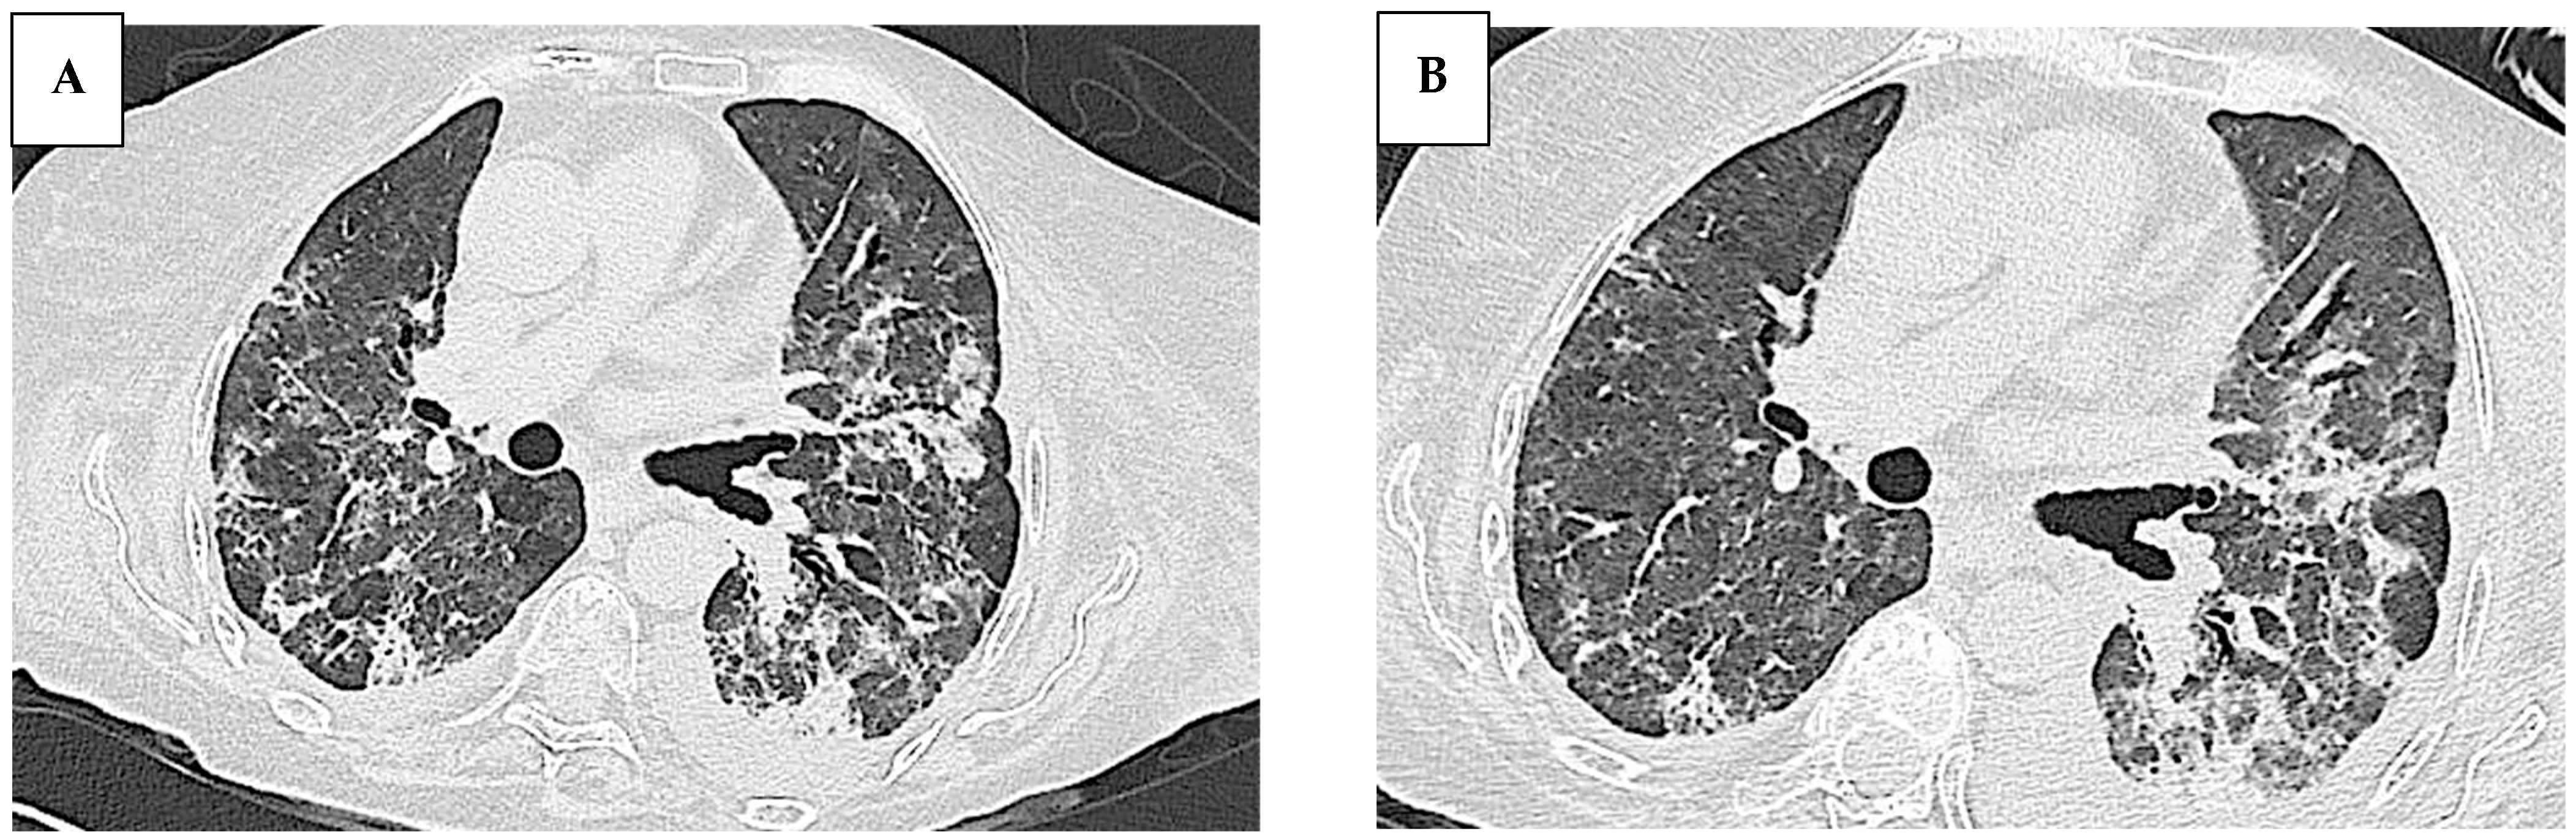

| Our patient | 68 | female | - ASyS - SD | - ANA (anti-Golgi pattern 1:1280) - anti Ro/SSA - anti PL-7 | - Raynaud Phenomenon: no - Arthralgia: no - Muscle weakness: no - Muscle enzyme elevation: no - Dyspnea: yes | NSIP | - Methylprednisolone bolus therapy (1 g/day for 3 days) - IVIG therapy (400 mg/Kg per day for 5 days) - Mycophenolate mofetil (3 g/day) - Nintedanib (300 mg/day) | The patient passed away 3 months after the initiation of immunosuppressive therapy |